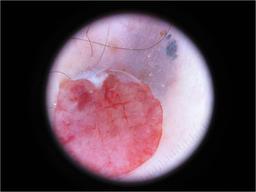

{

"age_approx": 60,

"anatom_site_general": "upper extremity",

"concomitant_biopsy": true,

"diagnosis_1": "Malignant",

"diagnosis_2": "Malignant melanocytic proliferations (Melanoma)",

"diagnosis_3": "Melanoma, NOS",

"diagnosis_confirm_type": "histopathology",

"image_type": "dermoscopic",

"melanocytic": true,

"sex": "female"

}